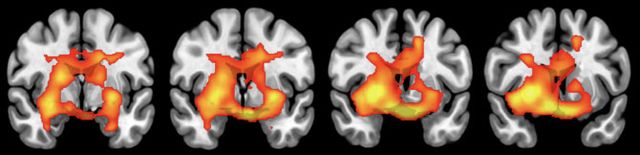

연구팀은 건강검진 프로그램에 참여한 대상자의 FDG PET 데이터를 기반으로 뇌 포도당 대사를 정량적으로 측정했다. 그 결과, 가구 소득 수준이 높을수록 미상핵(caudate), 피각(putamen) 등 보상 기전에 관여하는 뇌 영역과 전대상피질(anterior cingulate), 해마(hippocampus), 편도체(amygdala) 등 스트레스 조절 기능을 담당하는 영역에서 대사 활성 증가가 뚜렷하게 나타났다.